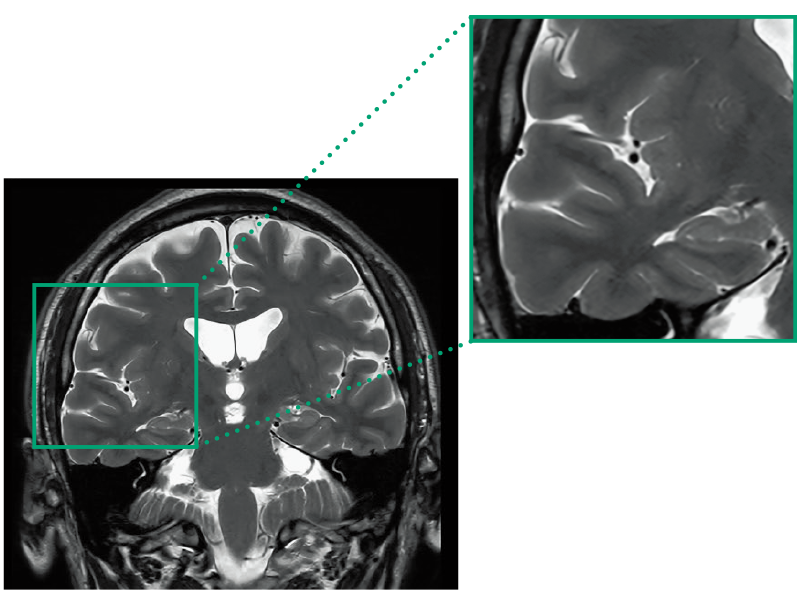

T2WI, 0.56×0.70×3.0mm, 2:28